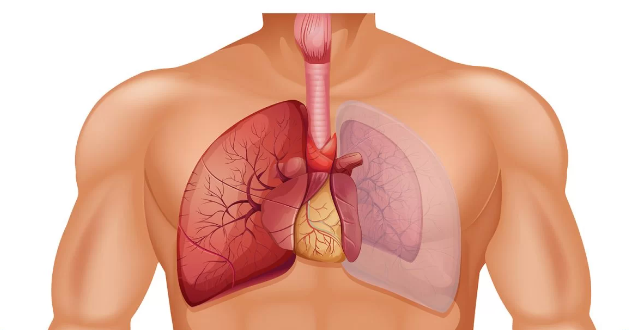

عوامل ایجاد کننده آمبولی ریه

آمبولی ریوی انسداد ناگهانی در عروق ریه است علت آن معمولا یک لخته خون در ساق پا به نام ترومبوز ورید عمقی است که این لخته می شکند و از طریق جریان خون به ریه ها وارد می شود.آمبولی ریه یک بیماری جدی است که می تواند سبب آسیب دائمی به ریه ی آسیب دیده، سطوح پایین اکسیژن در خون و آسیب به ارگان های دیگر بدن در اثر نرسیدن اکسیژن کافی به آن شود.البته در اغلب موارد، لخته های خون کوچک هستند و مرگبار نیستند اما آنها می توانند به ریه ها آسیب برسانند.